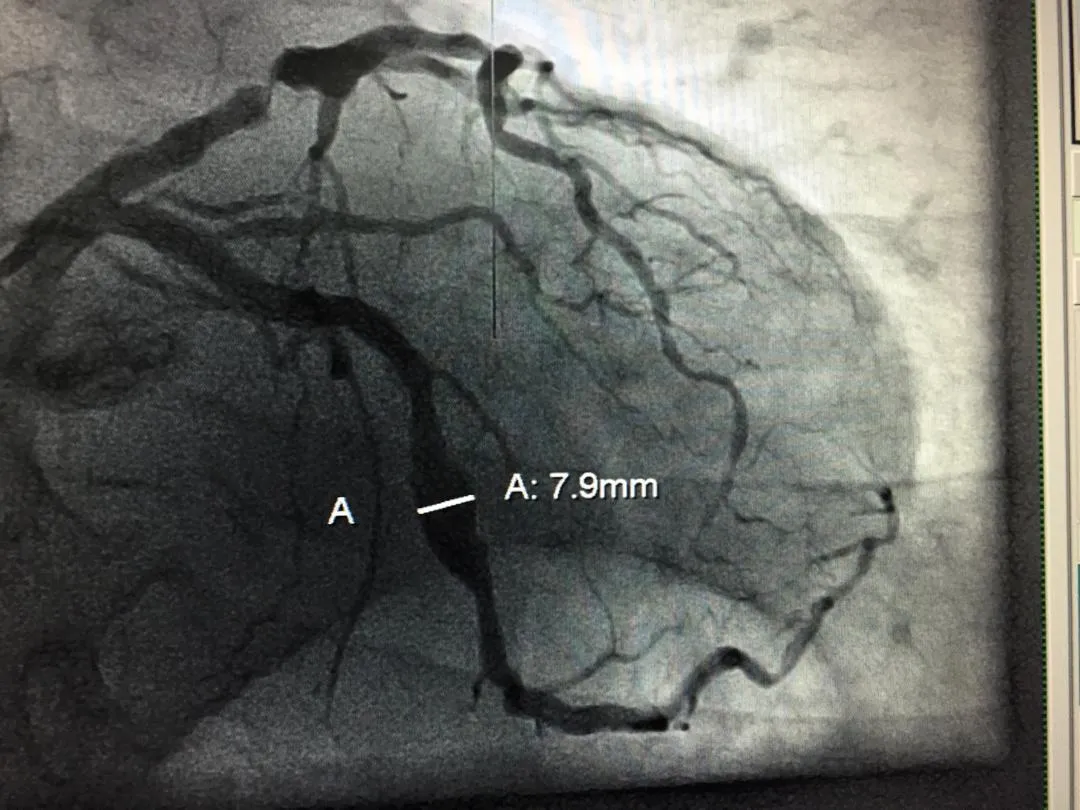

Los cateteres son introducidos a través de la arteria para ser llevados hasta las arterias que serán estudiadas, si el caso es un infarto del miocardio, serán llevadas hasta las arterias coronarias. Una vez allí se inicia la inyección a través del catéter de una sustancia radiopaca llamada contraste, lo que permite observar a través de que arterias esta pasando la sangre de forma adecuada y en cuales no. Esto es posible mediante un control radiográfico que se hace en el exacto momento de la inyección del contraste.

La mayoría de las veces al hablar de cateterismo cardíaco se asocia al corazón y al estudio de las arterias coronarias, pues inicialmente el estudio se diseño con esta finalidad y basado en la perfección de la técnica se fue adecuando al nacimiento de nuevas tecnologías y mejoría en los materiales empleados, como los cateteteres, guías, introductores etc.

El desarrollo del cateterismo cardíaco paso de ser algo mayormente diagnóstico a una técnica que ofrecía una alternativa terapéutica, de allí se fue perfeccionando la angioplastía coronaria donde se ofrecia la posibilidad de aperturar aquellas arterias obstruidas mediante el inflado de un balón dentro de su luz y el implante de unas mallas de aleaciones de bario que restituia el paso de sangre llamados Stent. Este Stent evoluciono desde permitir la liberación controlada de farmacos para evitar el rechazo como cuerpo extraño, hasta ser un elemento que se reabsorve.